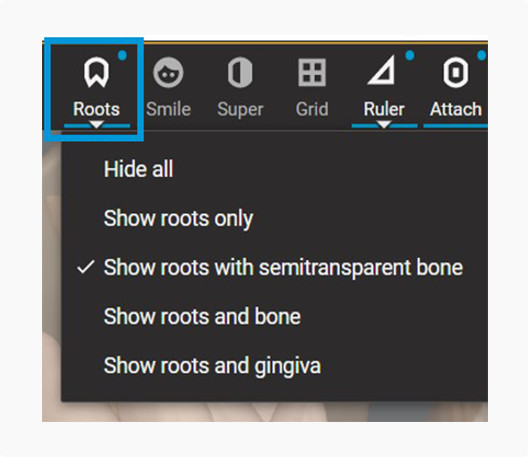

Start your treatment planning process in ClinCheck Pro leveraging the now enabled “Roots” button in the tool bar.

Start your treatment planning process in ClinCheck Pro leveraging the now enabled “Roots” button in the tool bar.

Three new views in one integrated platform to enhance treatment planning.

Roots only

Roots with semitransparent bone

Roots and bone

Roots only

Roots with semitransparent bone

Roots and bone